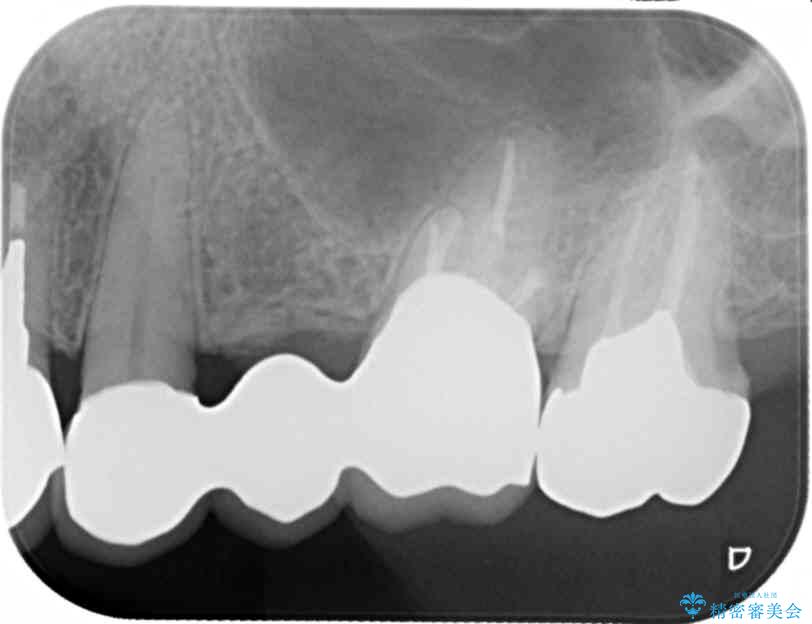

まず検査を行い、歯周病や歯内の問題がないことを確認しました。

銀歯をジルコニアセラミックへと換えることで、審美性・清掃性の高い仕上がりを目指します。

ブリッジに審美的でないイメージやあまり良くないイメージをお持ちの方を多々お見受けしますが、適切な設計とすることで、見た目に自然で審美的なブリッジ治療を行うことができます。